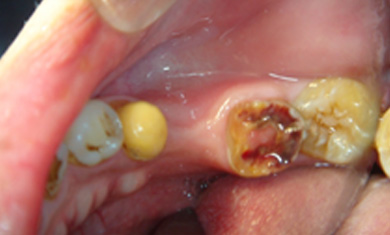

拆下牙橋後